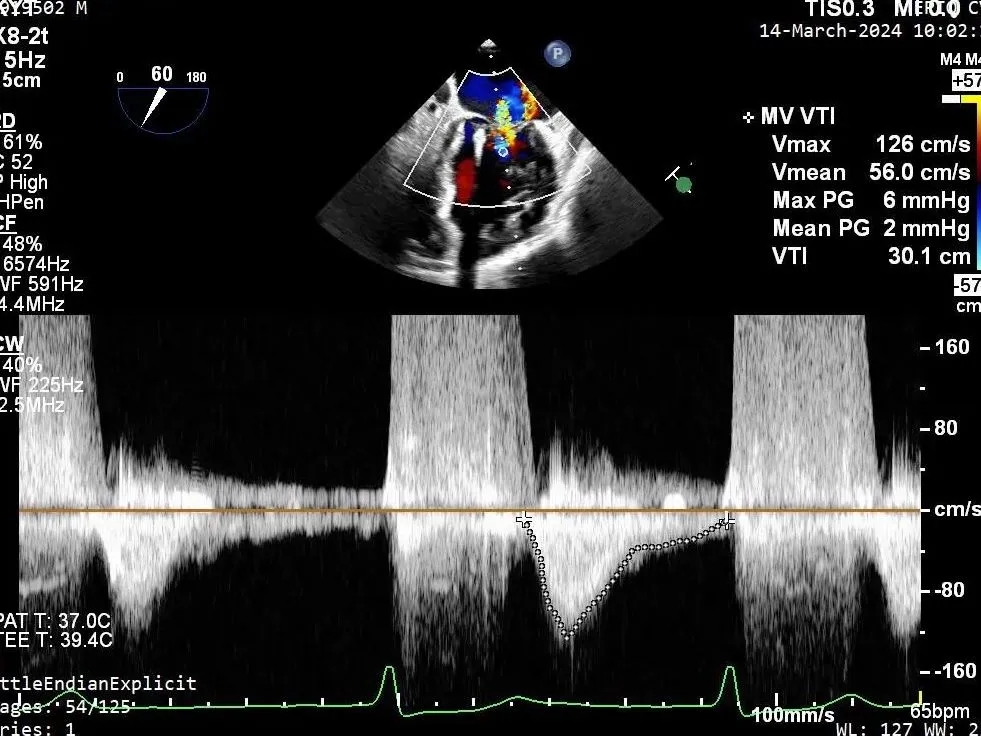

瓣膜夹释放前评估,二尖瓣平均跨瓣压差及瓣口面积

第二个瓣膜夹释放前评估,二尖瓣平均跨瓣压差及瓣口面积

第三个瓣膜夹释放前评估,二尖瓣平均跨瓣压差